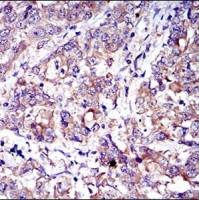

Bax基因是人体最主要的凋亡基因,属于Bcl-2基因家族,编码的Bax蛋白可与Bcl-2形成异二聚体,对Bcl-2产生阻抑作用,研究发现Bax/Bcl-2两蛋白之间的比例关系是决定对细胞凋亡抑制作用强弱的关键因素,因此认为,Bax是极重要的促细胞凋亡基因之一。Bax的表达更为广泛,它可出现在肝细胞、肾小管上皮细胞、呼吸系上皮细胞和支气管平滑肌、血管平滑肌细胞中。

- 阳性部位:胞质

- 适用组织:石蜡切片/冰冻切片

- 预处理:热修复